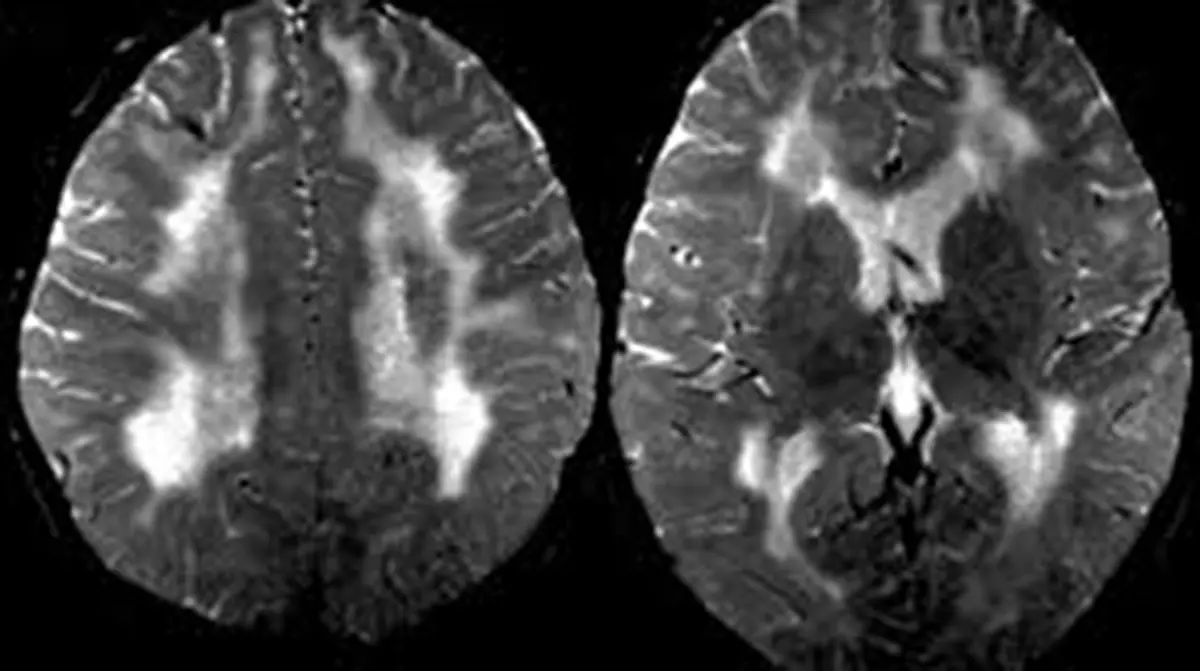

SSPE is a progressive and fatal brain disease caused by persistent infection with the measles virus. It usually develops years after a person has recovered from measles – often in childhood – and results from an abnormal immune response that allows mutated viruses to remain in the brain. Although very rare, the disorder almost always leads to severe neurological decline and death.

• Progressive stage: Involuntary jerking movements, muscle spasms, seizures, vision problems and deterioration of motor skills develop as the disease progresses.

• Advanced stage: Patients become bedridden, lose the ability to speak or swallow, and may fall into a vegetative state. Blindness, coma and recurrent infections are common.